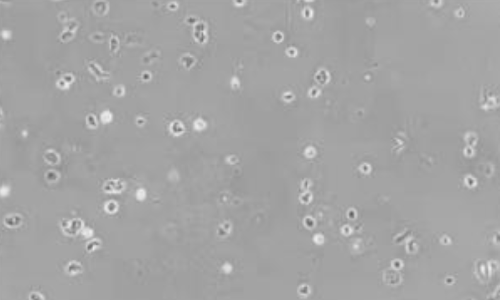

▲人胶质瘤 FFPE 样本 |